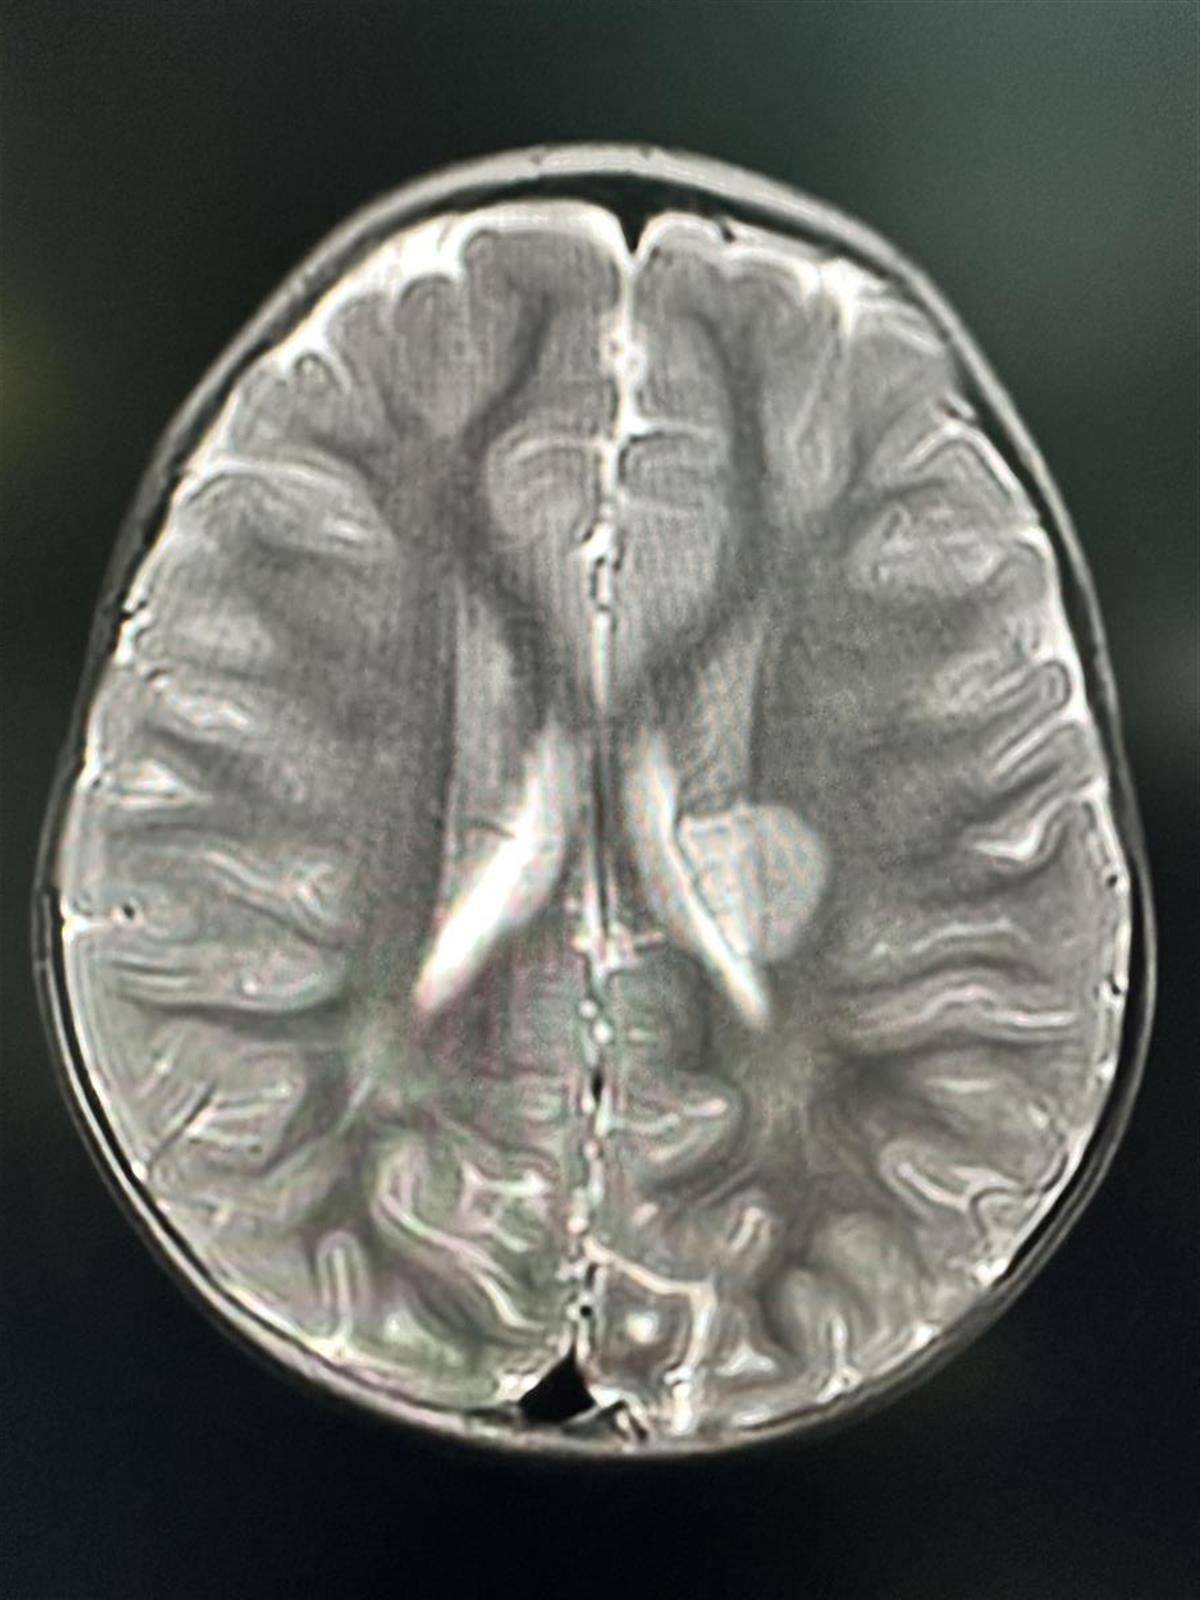

1、没想到小孩也会中风,一直以为中风这两个字只会出现在大人身上,没想到这么小的小孩也会中风,真是闻所未闻。